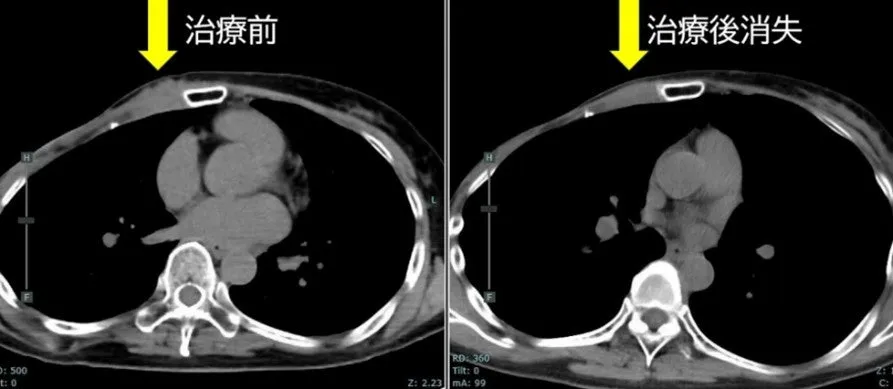

• - 再発乳がんのケース(治療4例目): 治療前の腫瘍は約37mmでしたが、3ヶ月後の評価で腫瘍が消失しました。腫瘍マーカーも著しく低下。

• - 初発乳がんのケース(治療10例目): FDG-PETでの集積が減少し、治療1ヶ月後には触診上腫瘍が確認できなくなり、その後の検査でも腫瘍が見られない状態が続きました。この成果により、完全奏功(CR)が達成されています。